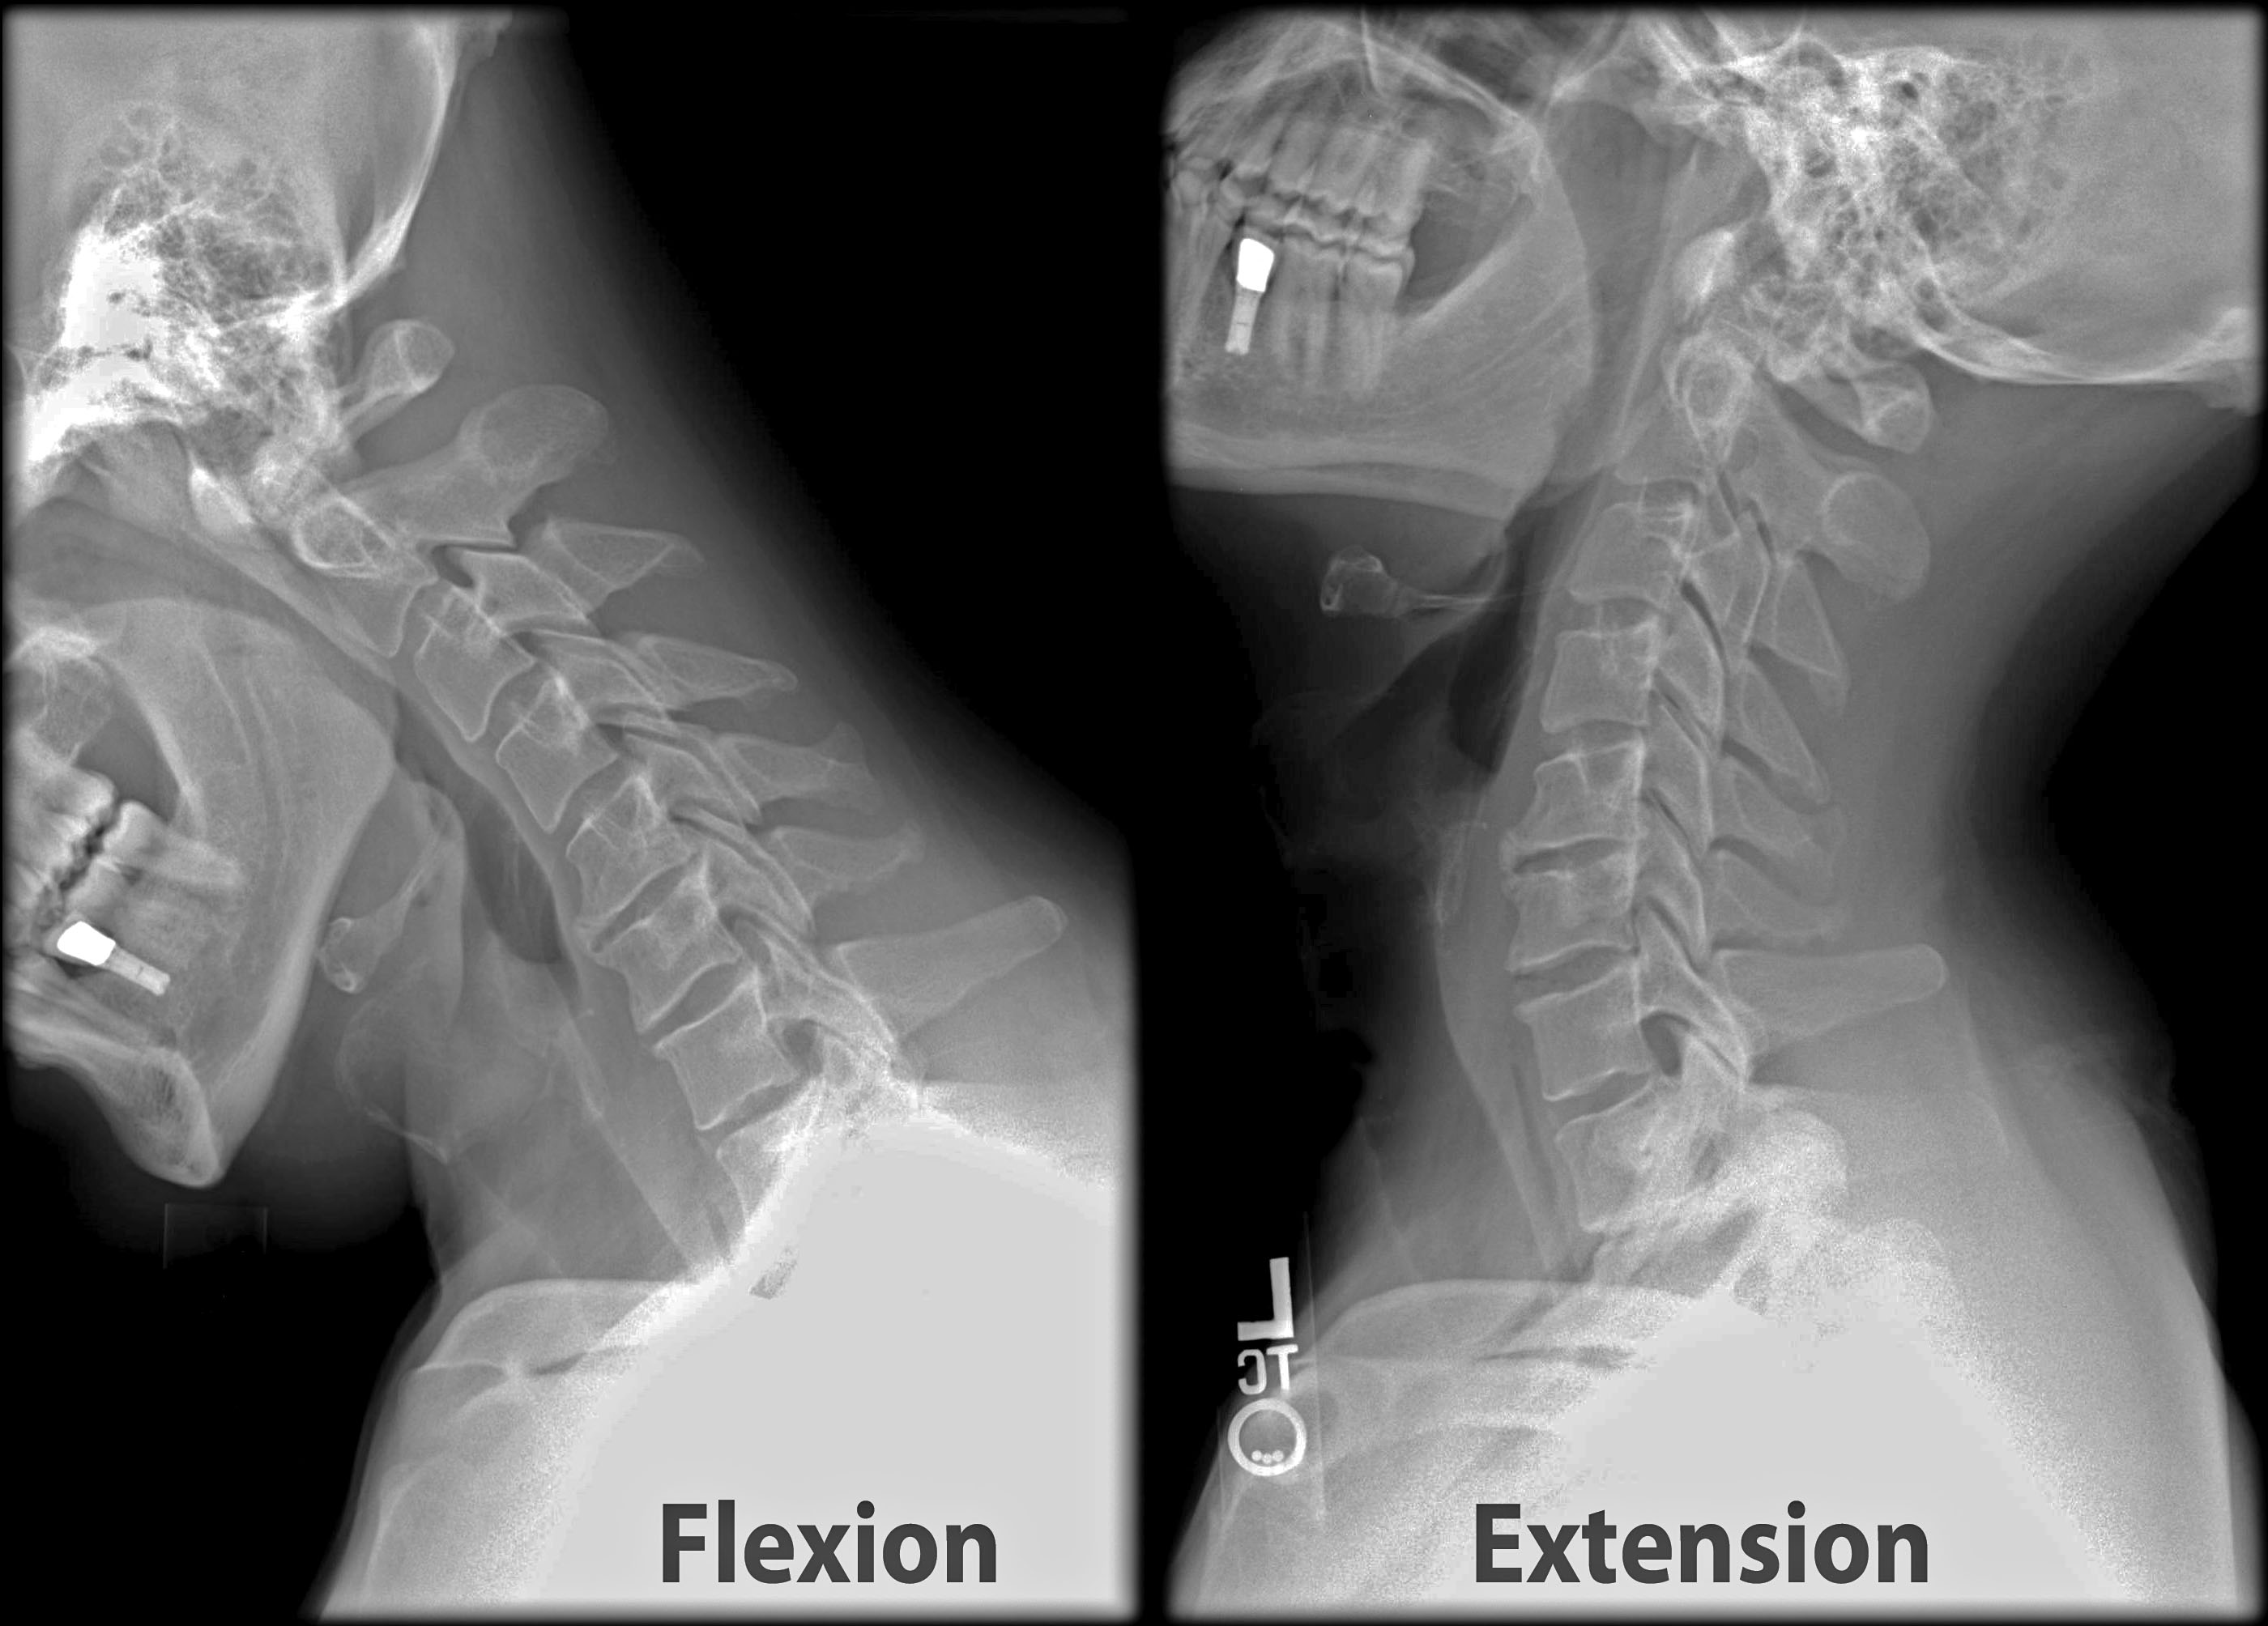

Your medical professional might likewise advise a series of imaging treatments to identify the cause of your pain in the back. These imaging treatments can consist of x-rays, bone scans, and CT scans. These imaging treatments can be handy, yet they aren't always necessary for the majority of situations of neck and back pain. If you have severe pain in the back, your physician might recommend an injection. These injections can help to ease pain as well as minimize inflammation.

A physiotherapist can help you find out to strengthen your core muscles, so you are less likely to experience an additional back injury. They can additionally instruct you how to do exercises at home. You may be instructed to do flexion and also extension exercises to reinforce the muscles that support the spinal column. You may likewise be instructed to do extending exercises to relax your muscle mass.

Your medical professional may additionally recommend a physical therapist. A physiotherapist can collaborate with you to help you develop a customized exercise program. They will also have the ability to assist you reinforce your core muscular tissues as well as various other sustaining muscular tissues. You might likewise be advised to do flexion as well as extension workouts, as well as you might be given a house exercise program.